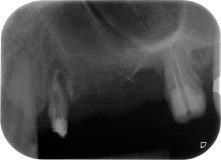

Накрая, след периостален разрез, мястото е пасивно зашито с коронарно напреднало ламбо, използвайки 5-0 абсорбиращ конец (Фиг. 15). Следоперативната рентгенова снимка показва, че и двата импланта са в правилна вертикална позиция (Фиг. 16).

Фигури 17 и 18 показват клиничния резултат два месеца след операцията. Зъб 24 показва намалена подвижност на Милър клас 1 и меките тъкани не са възпалени. Сондирането е избегнато на този етап, за да се избегне повторно възпаление и нарушение на епителната надстройка. Планиран е контролен преглед за повторно отваряне и поставяне на оздравителни абатмънти, шест месеца след поставяне на имплантите.